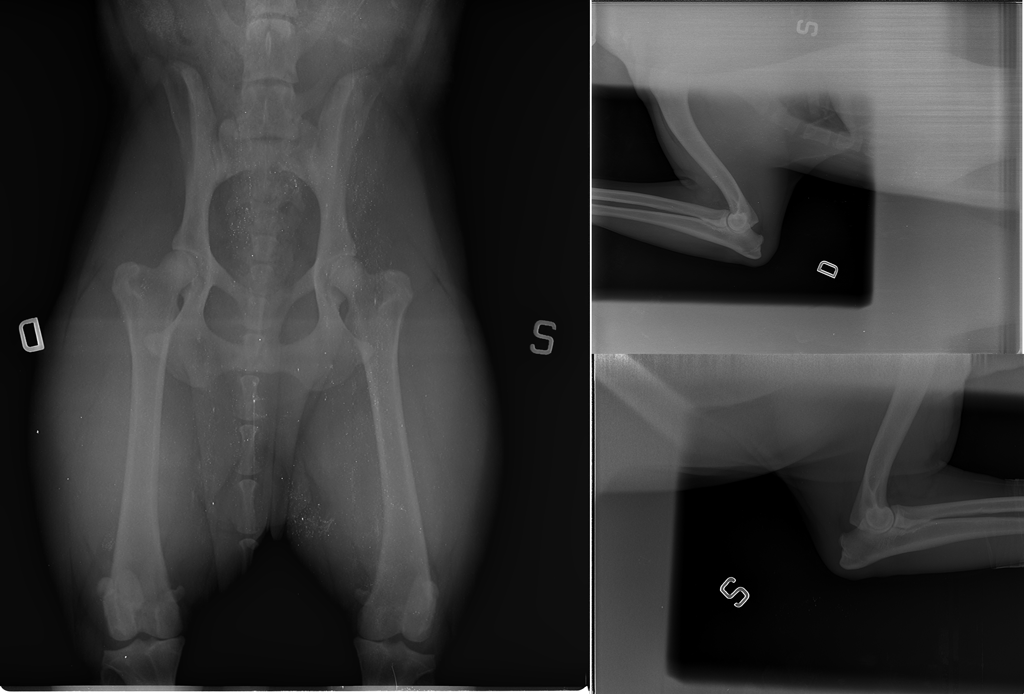

HDB – ED0

COD AJAHMW1Z – PW QJ4K5

Inka X-Ray page @ Celemasche

COD. XAMGXKRS- PW. I1FHH